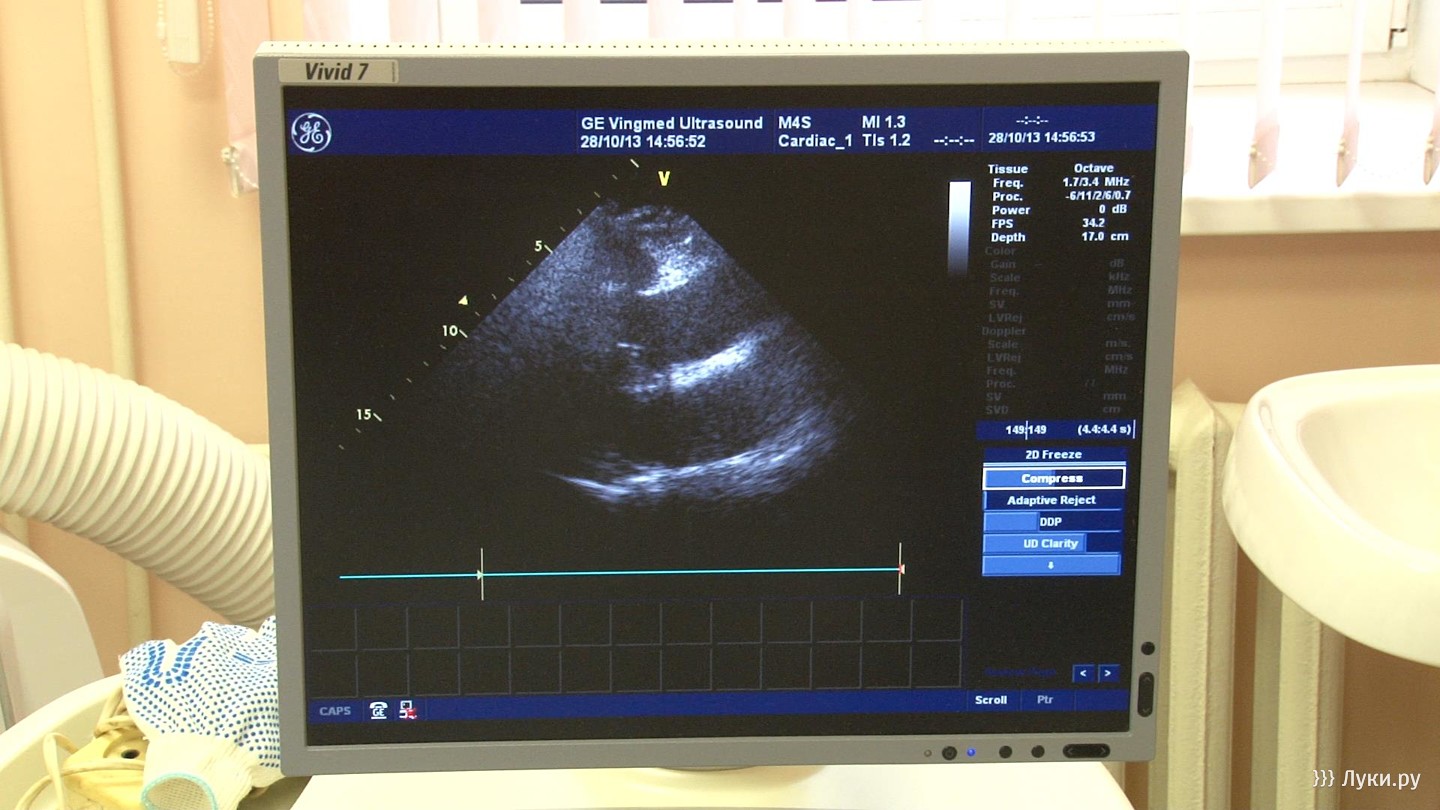

Общество Новый заведующий кардиологическим отделением приступил к работе в великолукской городской больнице 29 октября 2013 17:00 7 5 фото